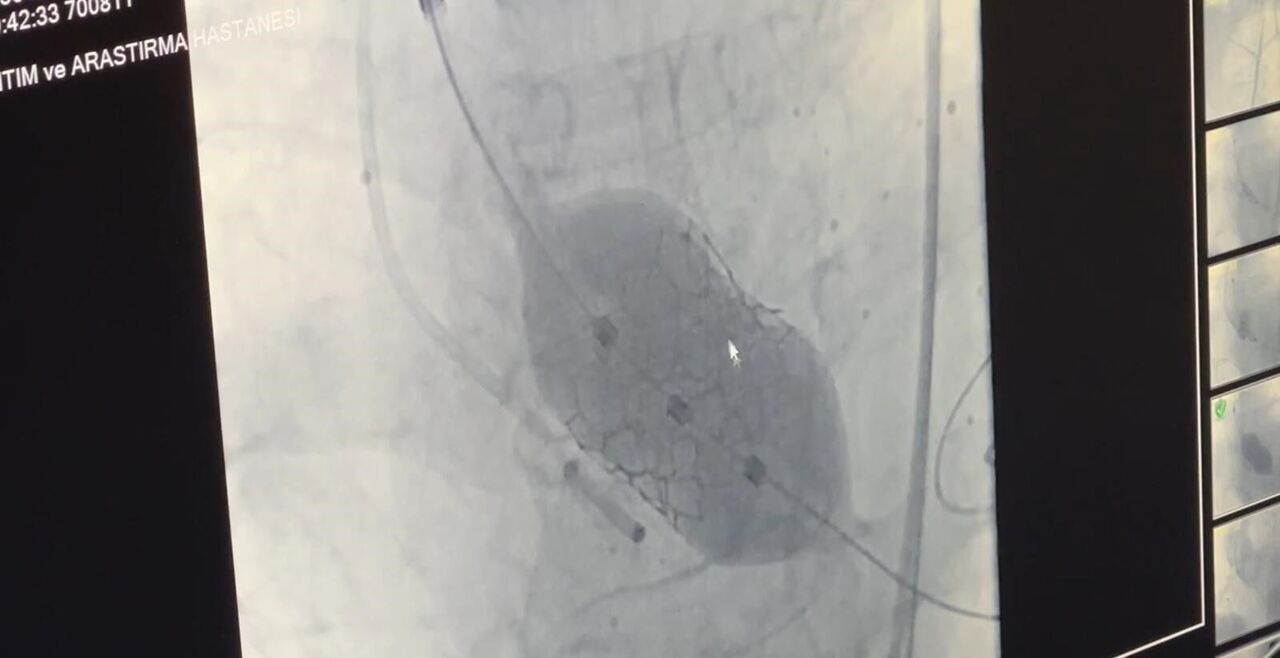

Doç. Dr. Yenerçağ, işlem öncesi yapılan tetkiklerde karşılaştıkları nadir bulgu hakkında ise "Hastanın TAVİ işleminden önce yapılan tetkiklerinde aort kapağının 3 yaprakçıklı olması beklenirken çok daha nadir görülen ‘Quadricuspid’ adı verilen 4 yaprakçıklı aort kapağı saptadık. Daha önce böyle bir vaka ile karşılaşmamıştık. Literatürleri, akademik çalışmaları inceledik. 4 yaprakçıklı aort kapağının toplumda 100 bin kişide 4 görüldüğünü, taradığımız uluslararası yayınlarda ise 4 yaprakçıklı aort kapağı bulunan sadece 17 hastaya TAVİ işlemi yapıldığını saptadık. Ülkemizden bildirilen vaka örneği bulamadık. Diğer ülkelerde yapılan vakaları detaylıca inceledik. İleri tomografik analizleri yaptık. Vakamıza detaylıca hazırlandık" dedi.

"Doç. Dr. Serkan Sivri, asistan doktorlarımız Berkan Öztürk ve Enes Kaya ile Anestezi Uzmanı Aynur Kaynar hocamızla beraber ekip halinde hastamıza başarılı TAVİ işlemini yaklaşık 50 dakika içerisinde tamamladık. Hastamızı 1 gün yoğun bakımda takip ettikten sonra servis takibine aldık. Nadir görülen bu 4 yaprakçıklı aort kapağına yaptığımız TAVİ işleminin prosedürel detaylarını literatüre kazandırmayı planlıyoruz. Bizden sonra bu nadir vaka ile karşılaşan meslektaşlarımıza yol göstermesi açısından referans olacaktır."